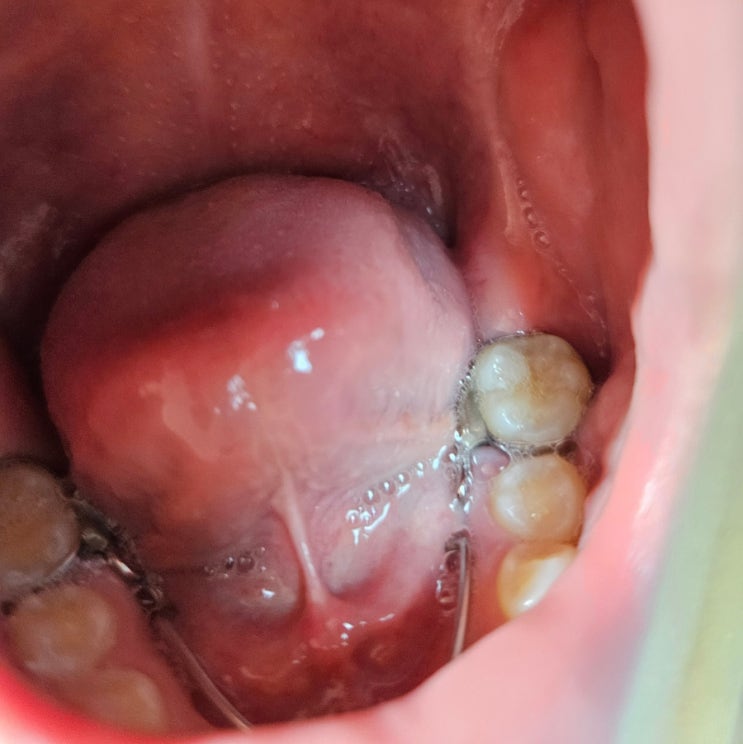

치아 공간유지장치 관리하기 : space maintainer

유전이라는 건 참 무서운 것 아드님이 아빠님을 쏙 빼 닮다 보니 어릴 때는 정교합이던 치열이 자랄 수록 ...